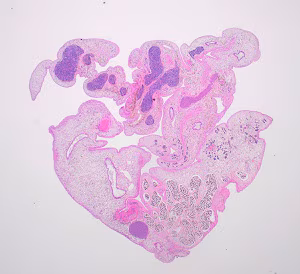

2019 DPDx Case Studies

DPDx is an educational resource designed for health professionals and laboratory scientists. For an overview including prevention, control, and treatment visit www.cdc.gov/parasites/.